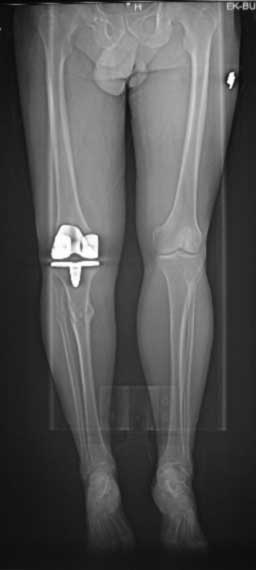

У пациента 50 лет имеется разгибательная контрактура через 8 меспосле ТКА. Уважаемые коллеги. Пациент 8 мес после операции ТКА, в анамнезе – неправильно сросшийся перелом голени, коррекция оси (снимки прилагаются. В настоящее время имеется разгибательная контрактура 10/5/0, на операционном столе было 90/0/5, на момент выписки движения 50/0/0 в надежде на дальнейшую разработку. До эндопротезирования 40/10/0. Глубокая инфекция исключена. Ротация бедренного компонента в норме (по КТ). Вопросы: насколько для такого ограничения критична некорректная установка б/б компонента (я намерял 7 град)? Причина нынешнего состояния, артрофиброз? Какие действия следует предпринять, удаление рубцов, релиз головок 4-главой мышцы? Что-либо другое, ваше мнение? С уважением, Максим Агалаков, Екатеринбург.

Рентгеновский снимок хороший, операция выполнена достойно, надколенник не смущает. Остаюсь на своем мнении, артролиз, если смущает давление надколенника при артроскопии помимо артролиза верхнего заворота, боковых каналов и переднего отдела, дополните латеральным релизом надколенника, чтоб уменьшить натяжение.

Низковат, соласен. Соориентируетесь при операции, если ограничивает движения, перенести бугристость или Z-образная тенотомия связки надколенника, артросокпический артролиз обязательно.